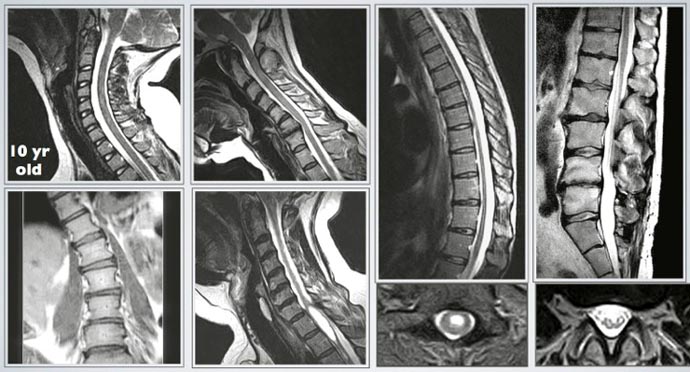

Spine Imaging